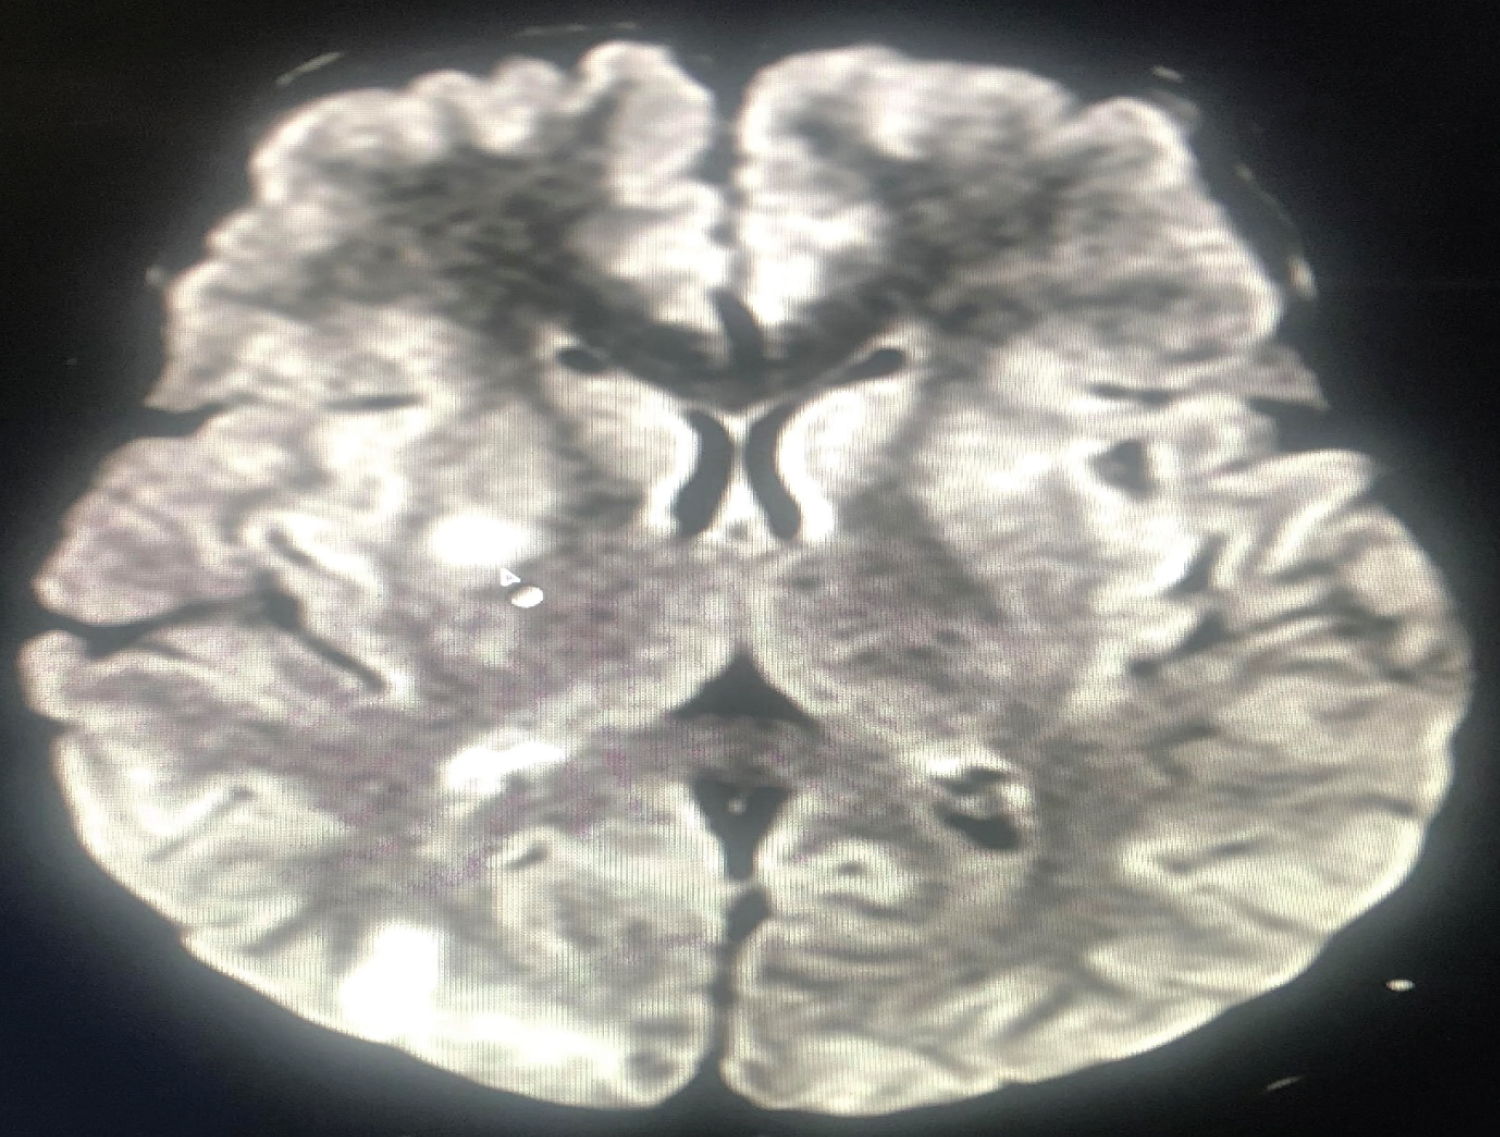

The first patient, a 20-year-old woman who underwent a caesarean section under spinal anaesthesia complained of a headache immediately after surgery and experienced a generalised tonic-clonic seizure 4 hours later. Vitals remained stable. Supplemental oxygen, midazolam, magnesium sulphate, levetiracetam, mannitol, furosemide, and steroids were used to treat the patient. The results of a brain MRI showed subcortical vasogenic edoema suggestive with PRES and bilaterally symmetrical areas of altered signal intensity in the fronto-parieto-occipital and right basal ganglia. Within 4 days, the patient had improved (Figure 1 and Figure 2).

Figure 2: MRI Brain depicting symmetrical areas of altered signal intensity in right parieto-occipital region. View Figure 2